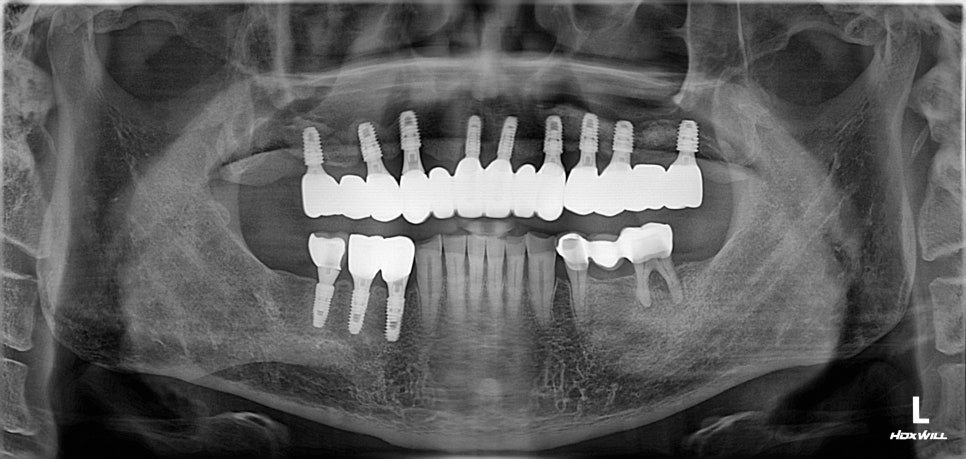

- 다수의 식립도 가능할까?

여러 부위에 임플란트가 필요한 경우,

매번 내원할 때마다 긴장과 구역질을

반복하는 것은 굉장히 힘든 일입니다.

그러나 수면마취(의식하진정법)을 활용하면

물론 한 번의 과정으로 진행할 수 있습니다.